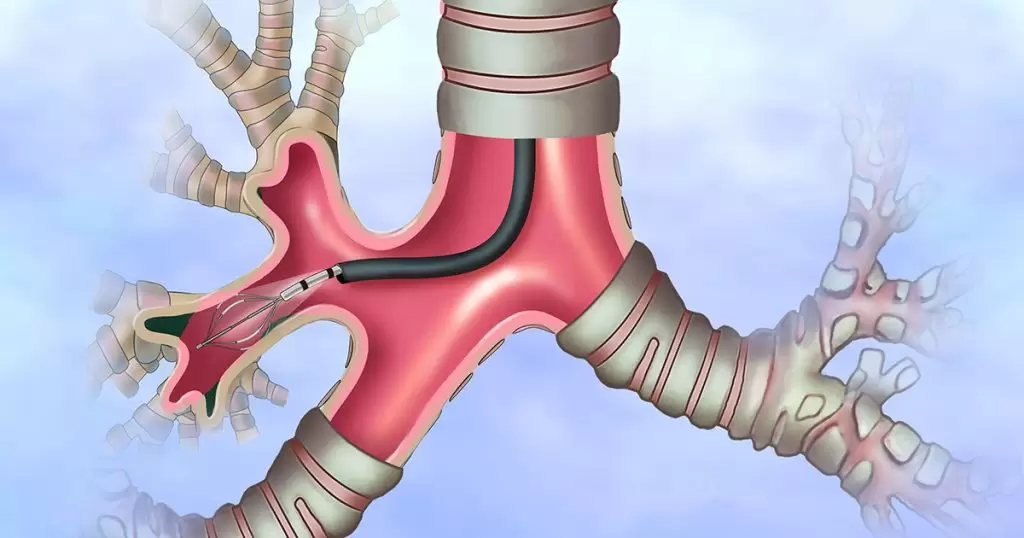

نەخۆشێک کە پێشتر تەنێکی نامۆ لە لوولەی سەرەوەی سییەکانیدا هەبووە، ٣ جار پشکنینی بۆرییەکانی هەناسەی بۆ کراوە و تووشی وەرەمێک بووە، بەڵام دوای ئەنجامدانی پشکنینی بۆرییەکانی هەناسە، بۆمان دەرکەوت کە ئەم تەنە نامۆیە هێلکە بووە.